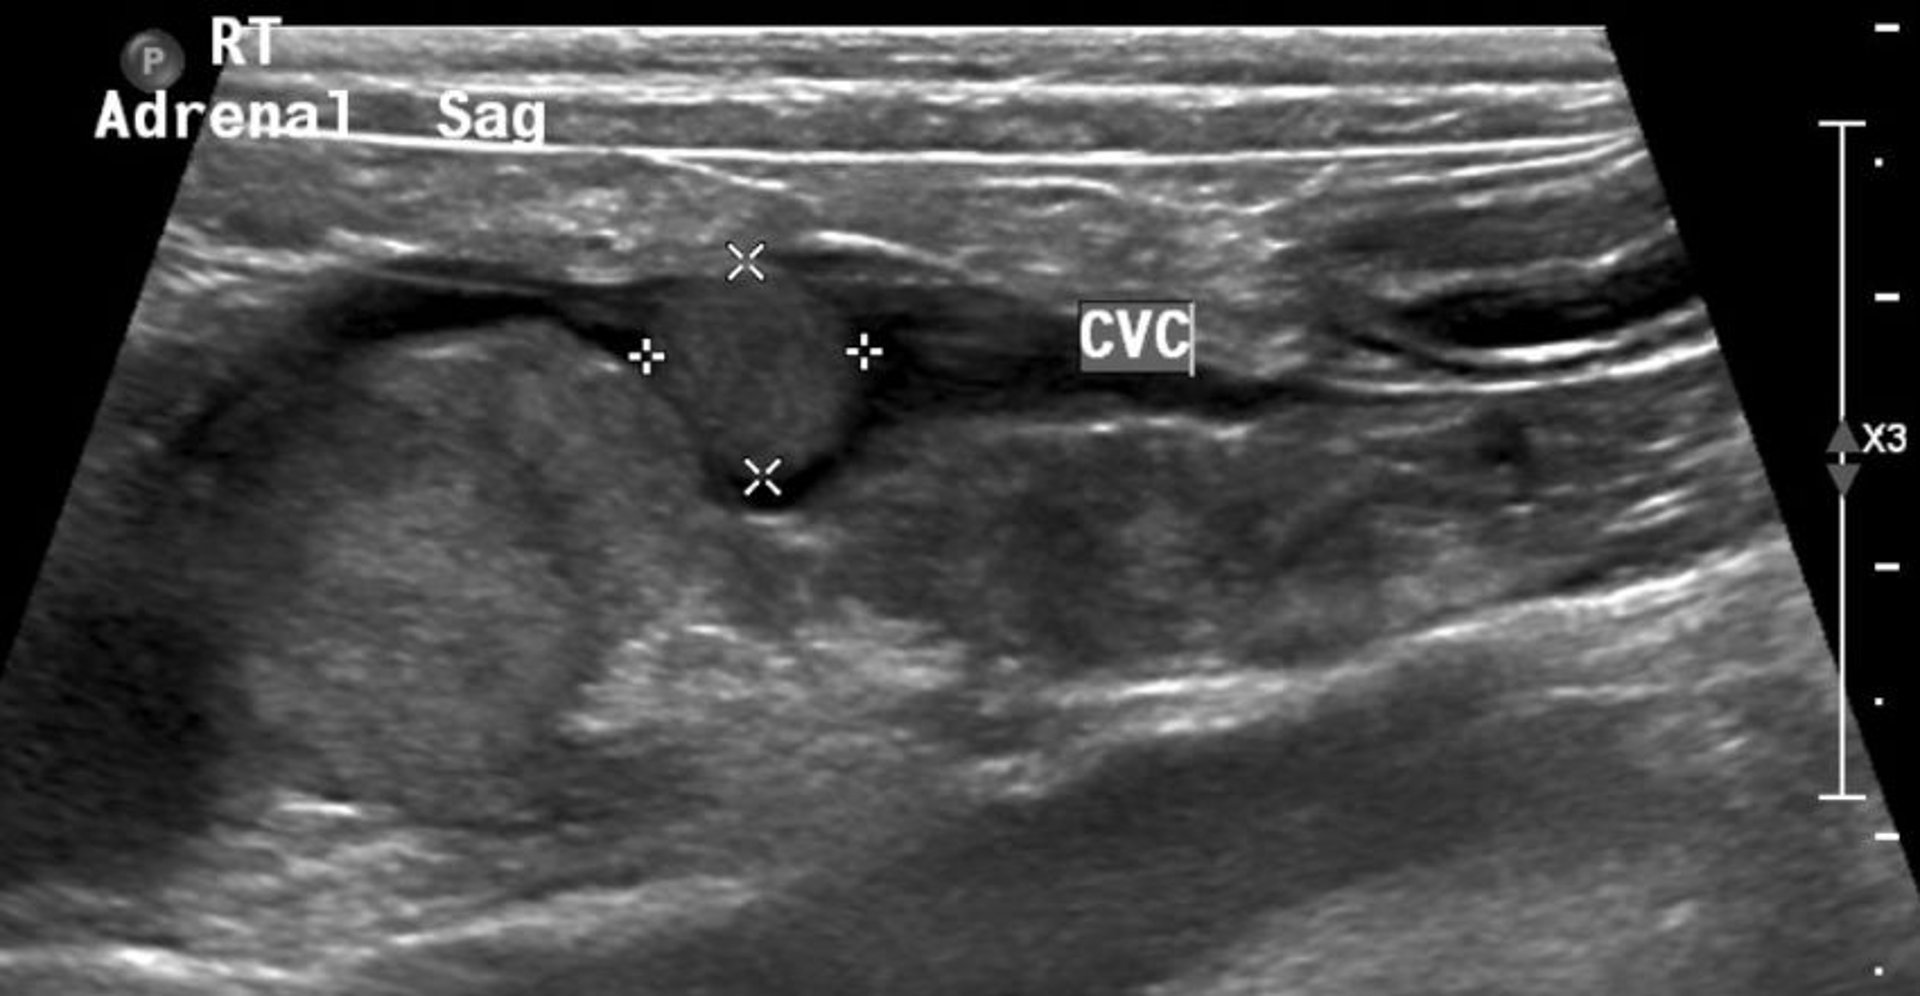

Adrenal tumor, ultrasonogram, dog

Sagittal-plane right cranial abdominal ultrasonographic image of a Dachshund, showing a large hyperechoic adrenal mass with lesion extension into the lumen of the abdominal caudal vena cava (cursors) that is causing partial occlusion. CVC, caudal vena cava.

Courtesy of Dr. Kristina Miles.